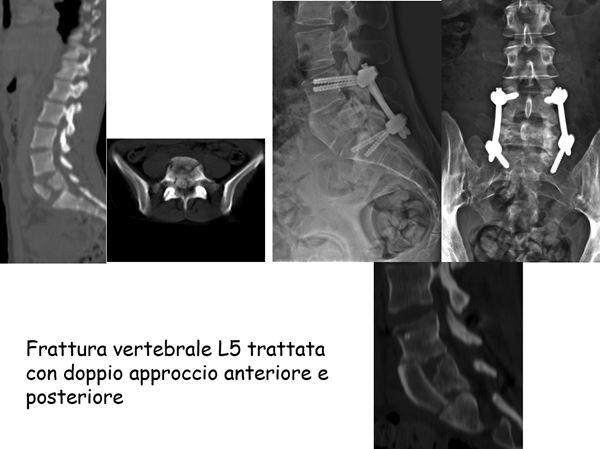

frattura vertebrale L5